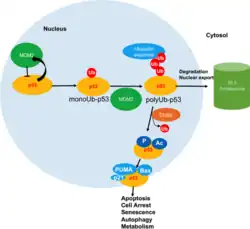

Decreased USF1-p53 interaction and increased p53 instability

The poor prognosis of gastric cancers is associated with low expression of USF1 and p53.[28] Among gastric cancer patients, 88% of the patients are diagnosed with H. pylori infection, and half of the patients show lower USF1 expression in tumor tissues. Mechanistically, H. pylori induces DNA hypermethylation in the promoter regions of USF1 and USF2 and inhibits expression. Decreased expression reduces the interaction between USF1 and p53 when DNA damage occurs, rendering p53 to associate more frequently with the E3-ubiquitin ligase HDM2 (also known as MDM2) and increasing p53 instability in cancer cells.[28]